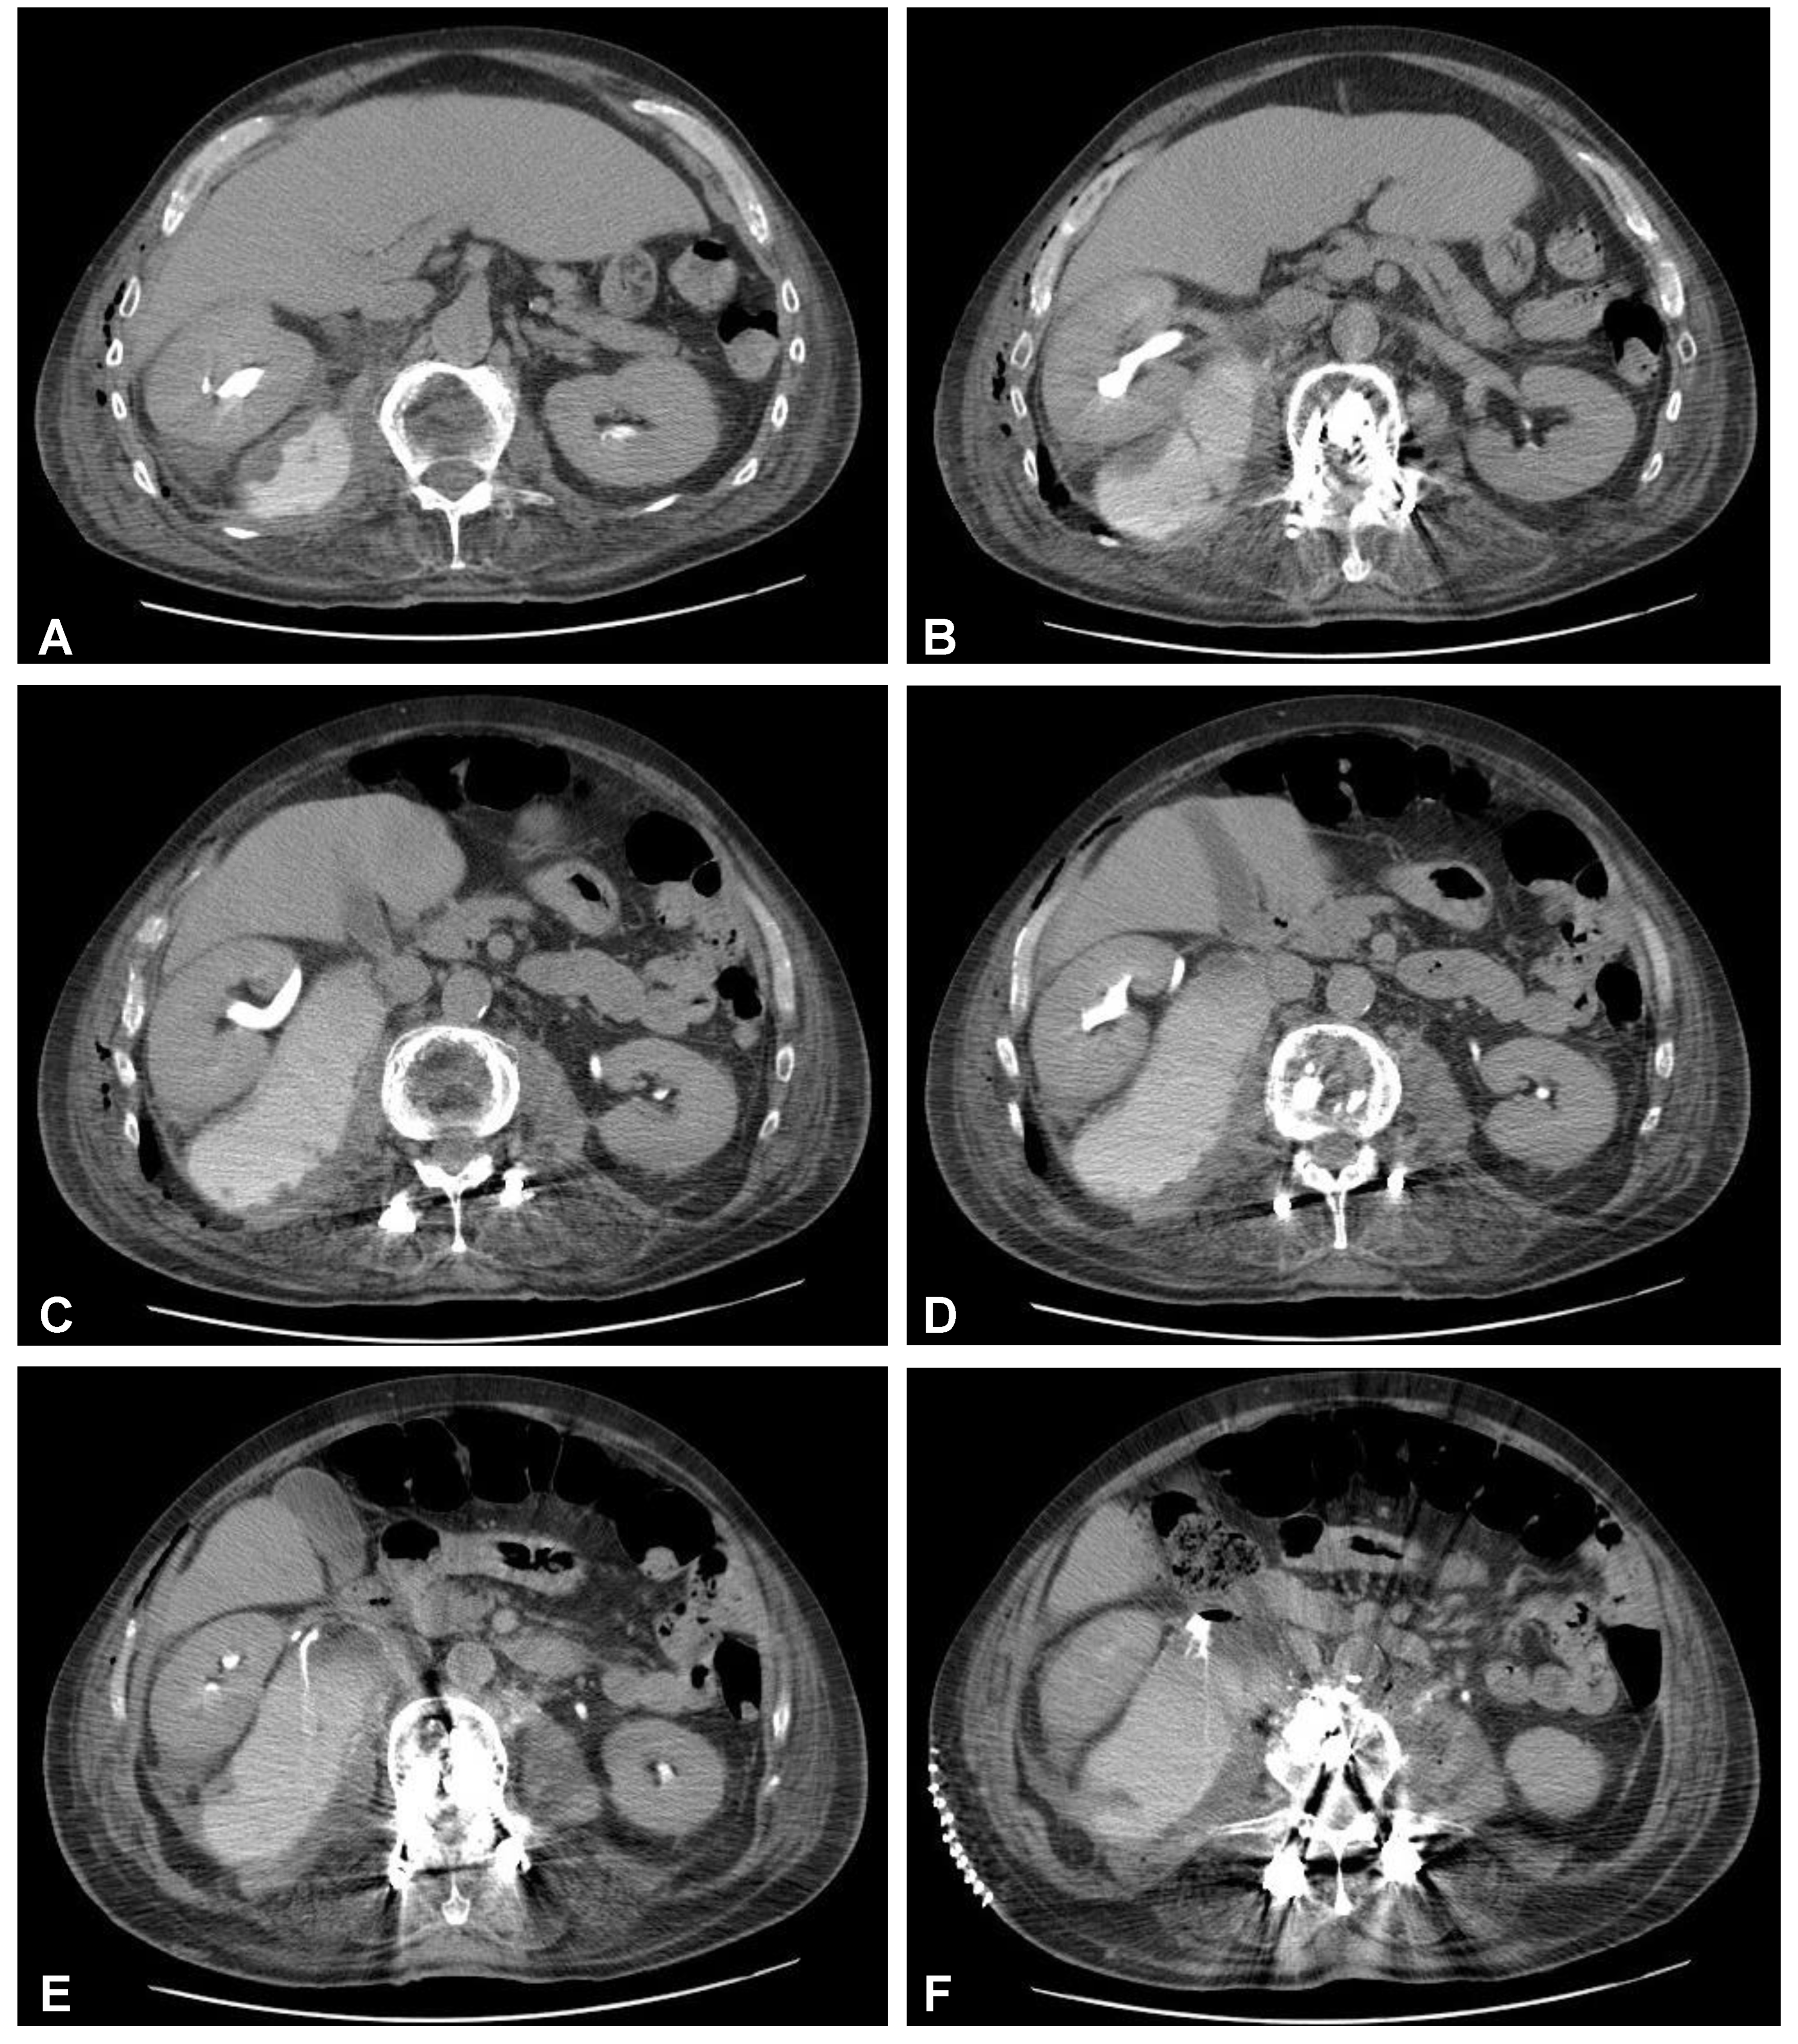

Figure 7. Postoperative axial CT scans (contrast enhanced delayed phase) demonstrating evidence of post-traumatic right ureteral injury, urine leakage, and hydronephroureter (AF).

After initial diagnostics and preparations, the patient was transferred to the operating room. The posterior percutaneous transpedicular stabilization at the L2-L3-L5-S1 levels (Mantis; Stryker, Kalamazoo, MI, USA) with cement augmentation (VertaPlex HV; Stryker, Kalamazoo, MI, USA) for each inserted screw (4 mm × 6.5 mm/50 mm; 4 mm × 6.5 mm/45 mm) under intraoperative 2-dimensional (2-D) fluoroscopy control was performed in the first stage of surgery. In the second stage of surgery, from a lateral approach, the left side of the retroperitoneal cyst was emptied, and watery/light yellow fluid similar to urine was obtained. Therefore, a distractible vertebral body replacement implant (AsterX; Medtronic, Minneapolis, MN, USA) was placed between the L3 and L4 bodies with the placement of a retroperitoneal precutaneus Redon drainage system. A control CT scan performed one day after the operation revealed the correct placement of all the implants (Figure 5 and Figure 6). The second CE-CT scan performed two days after surgery consecutively showed evidence of post-traumatic right ureteral injury, urine leakage, and hydronephroureter (Figure 7). The general examination of intraoperatively obtained fluid revealed the following results: pH: 9.0; protein: 600 mg/dL; transparency and color before centrifugation: sanguine and cloudy; transparency and color before centrifugation: transparent and dark yellow; absolute leukocytes (LEU): 1197 cells/μL; and sediment: single round epithelium in the sample with erythrocytes loosely cover the field of vision (15–20 in the counterfield). The microbial culture of the intraoperative obtained fluid after 7 days was negative. After 4 days, the patient was transferred to another local hospital specializing in urological care. Due to the overall late presentation covering advanced hydronephrosis, ureteric stricture formation, and non-functional kidney, the nephrectomy and ureter ligation were performed. After urological treatment, the patient has been on follow-up for 2 years with no evidence of neurological or urological problems.